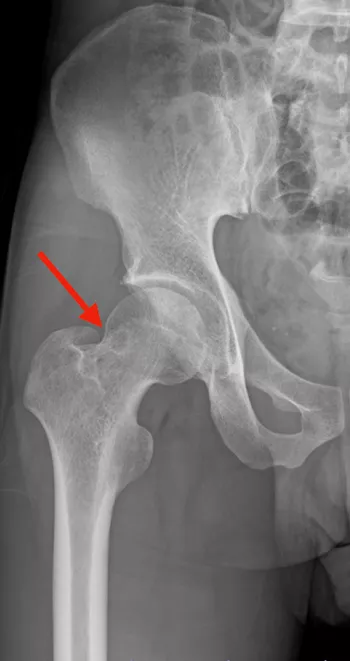

股関節単純X線正面像を示す(写真1)。

大腿骨頭頚部移行部に骨皮質下透亮像(赤矢印)を認める。